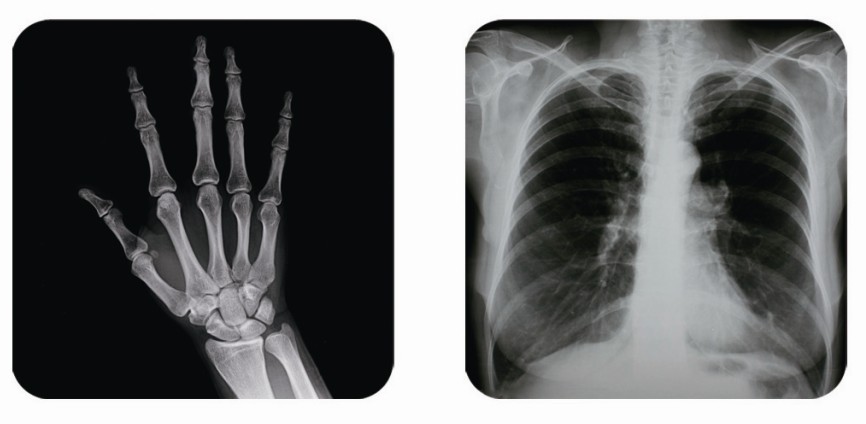

傳統(tǒng)胃腸造影檢查,病變顯示率低,輻射劑量大。普朗醫(yī)療器械公司生產(chǎn)的幾款多功能腸胃造影x光機,更能滿足不同等級不同規(guī)模的大小醫(yī)院選擇,從臨床及科研都很好。尤其最新的PLD8800多功能腸胃造影x光機用途更為廣泛。多功能腸胃造影x光機是目前各大醫(yī)院最普及的且用途最廣的一種X光機。普朗醫(yī)療的胃腸機功能多,簡便易用,能保證圖像質(zhì)量,該機采用高制式電視系統(tǒng),優(yōu)秀的數(shù)字化系統(tǒng)能使多功能腸胃造影x光機的性能得到提高,應用范圍獲得極大的拓寬。     如果您想了解多功能腸胃造影x光機價格多少錢,普朗醫(yī)療作為多功能腸胃造影x光機品牌廠家,報價肯定會比進口產(chǎn)品要優(yōu)惠很多。具體詳情,您可以點擊頁面漂浮的在線客服圖標,進行在線咨詢。同時,普朗醫(yī)療也可以給您簡單介紹一下關于多功能腸胃造影x光機的主要臨床應用:     1、一般應用:數(shù)字透視,動態(tài)及多方位觀察器官病變,圖像更清晰,并可保留末幀圖像;既可使用暗盒完成常規(guī)X線拍片,這是其最大的優(yōu)勢,拍片質(zhì)量大大提高。     2、特殊檢查的應用:如“T”管造影、消化道鋇餐、靜脈腎盂造影、子宮輸卵管碘油造影等,在實時監(jiān)視的同時隨時采集,抓住關鍵圖像,并可連續(xù)采集,電影回放整個過程。     3、介入方面的應用:能很好開展全身各部位的血管造影、藥物灌注、栓塞治療及經(jīng)皮穿刺活檢引流,主要應用于血管造影診斷及腫瘤的治療,不明原因腫塊的性質(zhì)確定。     相信普朗醫(yī)療生產(chǎn)的多功能腸胃造影x光機將為各醫(yī)院提供更為廣泛的臨床用途,創(chuàng)造更為可觀的經(jīng)濟效益。

(普朗醫(yī)療品牌——直接數(shù)字化醫(yī)用診斷X射線機PLD8800(多功能腸胃造影x光機))